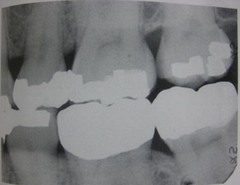

Rampent caries

Front

Back